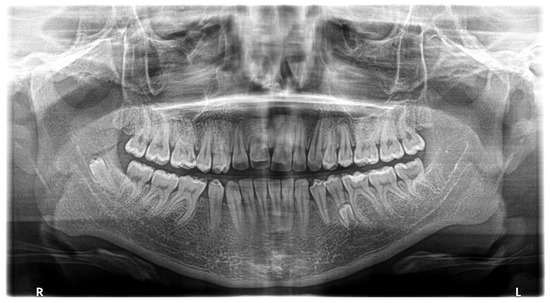

Tooth Migration in a Female Patient with Hyperdontia: 11-Year Follow-Up Case Report

2. Case Report